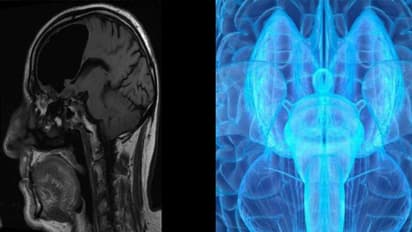

ബ്രയിന് സ്കാനര് നിര്മ്മിക്കാനൊരുങ്ങി ചൈന. ലോകത്ത് ഇന്നേവരെ നിര്മ്മിക്കപ്പെട്ടതില് ഏറ്റവും ശക്തമേറിയതായിരിക്കും ചൈന നിര്മ്മിക്കുന്ന ബ്രെയിന് സ്കാനര് എന്നാണ് ഗവേഷകര് പറയുന്നത്. മനുഷ്യന്റെ തലച്ചോറിലെ ന്യൂറോണിന്റെ ചലനങ്ങളും പ്രവര്ത്തനങ്ങളും ഈ ഉപകരണം കൊണ്ട് രേഖപ്പെടുത്താനുമാവും. നൂറു കോടി യുവാനായിരിക്കും ചെലവ്. ഗുവാങ്ടോങ് പ്രവിശ്യയിലെ ഷൈന്ചെനിലാണ് പദ്ധതിയുടെ പ്രവര്ത്തനങ്ങള് നടക്കുന്നതെന്നാണ് അറിയുന്നത്. കൂടുതല് വിവരങ്ങള് പുറത്തുവിടാന് ചൈന തയ്യാറായിട്ടില്ല. പക്ഷെ, പദ്ധതി നടപ്പിലാക്കാനുള്ള ആദ്യഘട്ടത്തിന് സര്ക്കാര് അനുമതി നല്കിയിട്ടുണ്ട്. ചൈനയിലെ പ്രശസ്ത ഭൌതികശാസ്ത്രജ്ഞന് സാഹോ സോങ്ങ്സിയാനാണ് ഇതിന്റെ ചുമതല.

സാധാരണ എം ആര് ഐ സ്കാനറുകള്ക്ക് 1.5 മുതല് 3 ടെസ്ല വരെയാണ് ശേഷി. യൂറോപ്പിലും യു.എസ്സിലും 11 ടെസ്ല വരെ രേഖപ്പെടുത്തുന്ന സ്കാനറുണ്ട്. നിലവില് യു.എസ്സില് 10 ടെസ്ലയും, ഫ്രാന്സില് 11 ടെസ്ലയും രേഖപ്പെടുത്താവുന്ന സ്കാനറുണ്ട്. എന്നാല്, 14 ടെസ്ല വരെ ശേഷിയുള്ള സ്കാനറായിരിക്കും ചൈന നിര്മ്മിക്കുക. തലച്ചോറിലെ ഓരോ ചെറിയ പ്രവര്ത്തനങ്ങള് പോലും ഇതിലൂടെ നിരീക്ഷിക്കാനാകുമെന്നും ഗവേഷകര് പറയുന്നു.